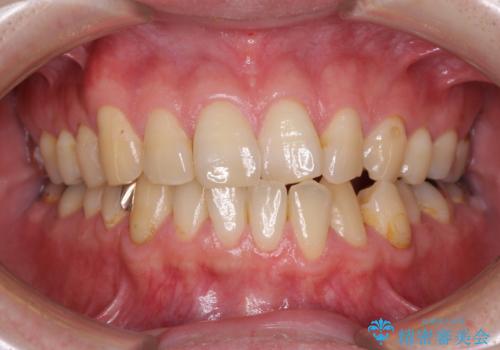

- デコボコした前歯をセラミックできれいに揃えたいとのことで来院された患者様です。

歯を削って整えることは簡単ですが、健全な歯を削って後悔してからでは遅いため、矯正治療を提案しました。

はじめは矯正治療の期間が長いことに悩んでいらっしゃいましたが、ある程度整えば満足するだろうとのことで、インビザラインにて矯正治療を行うこととしました。

左上の犬歯が欠損しているため、正中の位置や奥歯の咬み合わせが理想的にならない点を了承していただきました。